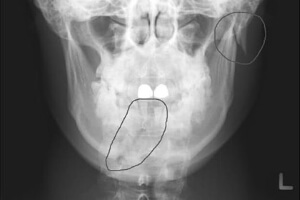

От степени тяжести зависит дальнейшее течение заболевания и его лечение. Для ее определения проведите диагностирование, предусматривающее проведение рентгенографии в 2 проекциях, по которым возможна идентификация травмы.

Врачи настоятельно предупреждают о рисках самостоятельного лечения перелома челюсти в домашних условиях. Несмотря на желание избежать медицинских учреждений, неправильное обращение с травмой может привести к серьезным осложнениям. Специалисты подчеркивают, что перелом челюсти требует профессиональной диагностики и лечения, включая рентгенографию для определения степени повреждения.